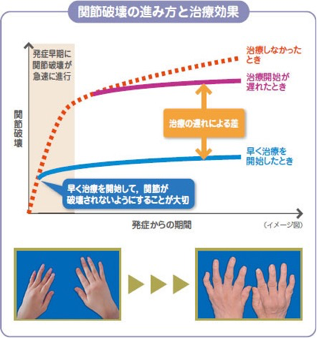

「朝のこわばり」、「手指の痛み・腫れ」が有名ですが、その他にも「肘」「膝」「足」「肩」など多くの関節に痛み・腫れが出てきます。またその状態を我慢してしまうと、関節の骨や腱が壊れてしまい、関節の変形を起こしてしまいます。

- ○最新のリウマチ検査・治療

- さて、そんな関節リウマチですが、ここ10年で診断と治療が目覚ましく進歩したのをご存知でしょうか?今まで難病のイメージの強かった関節リウマチですが、リウマチになっても仕事や家事をそのまま続けることが出来たり、お子さんを妊娠・出産されたり、元気に活躍されているリウマチの方が増えてきました。

以前は有効な治療薬がなく、「痛み止め」や「ステロイドホルモン剤」で痛みを和らげることしかできず、多くの患者さんが痛みを完全に良くできないばかりか、リウマチの進行が止められずに手指が曲がり、肘・膝が脱臼したりして整形外科で手術をされたり、残念ながら寝たきりの状態になってしまっていました。

しかしここ10年で「生物学的製剤」ができたことで、リウマチの痛みをとるだけでなく、関節で悪さしている免疫細胞を落ち着かせて骨の破壊や関節変形を起こさない治療ができるようになりました。生物学的製剤の中には、妊娠・授乳中も使用できる薬もあり、今まで妊娠中はステロイドホルモン剤が中心であった治療も大きく変わっています。

リウマチは昔のように早期に診断ができず有効な治療薬がなく、痛みに耐えて寝たきりになってしまう病気では決してありません。あまり心配されずに、いつでもご相談ください。